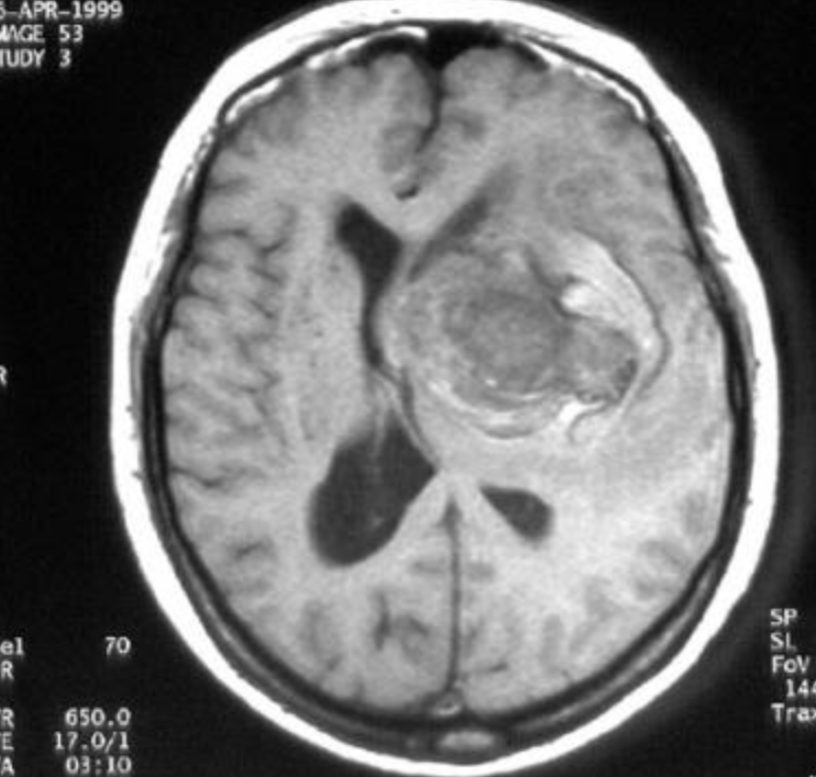

Aneurysm Rupture Prediction

Developing equations to predict the multivariable rupture of cerebral aneurysms. Supported by my 9th grade biology teacher, Mrs. Pat Kite, in 2015-16.